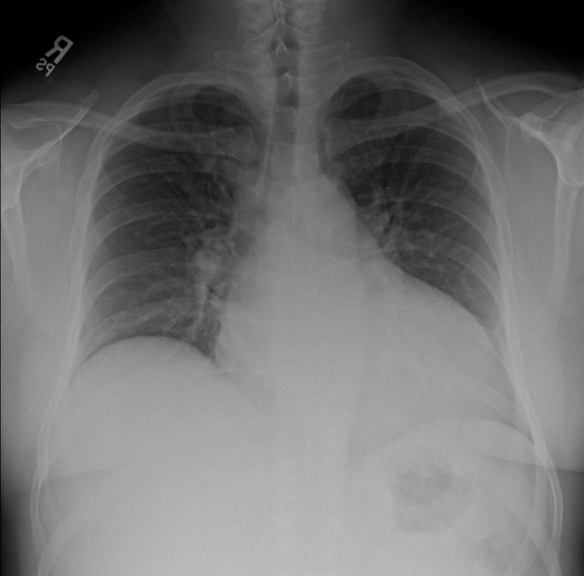

Screen Shot 2013-08-22 at 6.21.37 PM

Though it was atypical for the patient to be hypotensive and tachycardic, the presence of a pericardial effusion without tamponade suggested aortic dissection to me.  My attending got on the phone to prepare to transfer the patient while I contacted the radiologist to clear the CT scanner.  Though I attempted to view the descending aorta and aortic outflow tract on a more focused echo in the brief interim through a parasternal approach, I was unable to obtain good windows.  The IVC was plump and the rest of the FAST was negative.  A quick Chest XR was done:

Screen Shot 2013-08-22 at 6.21.01 PM

…..which did not show a wide mediastinum according to radiology.  The patient was whisked away to the CT scanner and within 45 minutes of ED arrival, the diagnosis of a Stanford type A aortic dissection with pericardial effusion (but not tamponade) was confirmed.  This would not have been possible without bedside ultrasound as I think most clinicians would have been falsely reassured by the normal CXR (widened mediastinum only present in 60% of aortic dissections1).